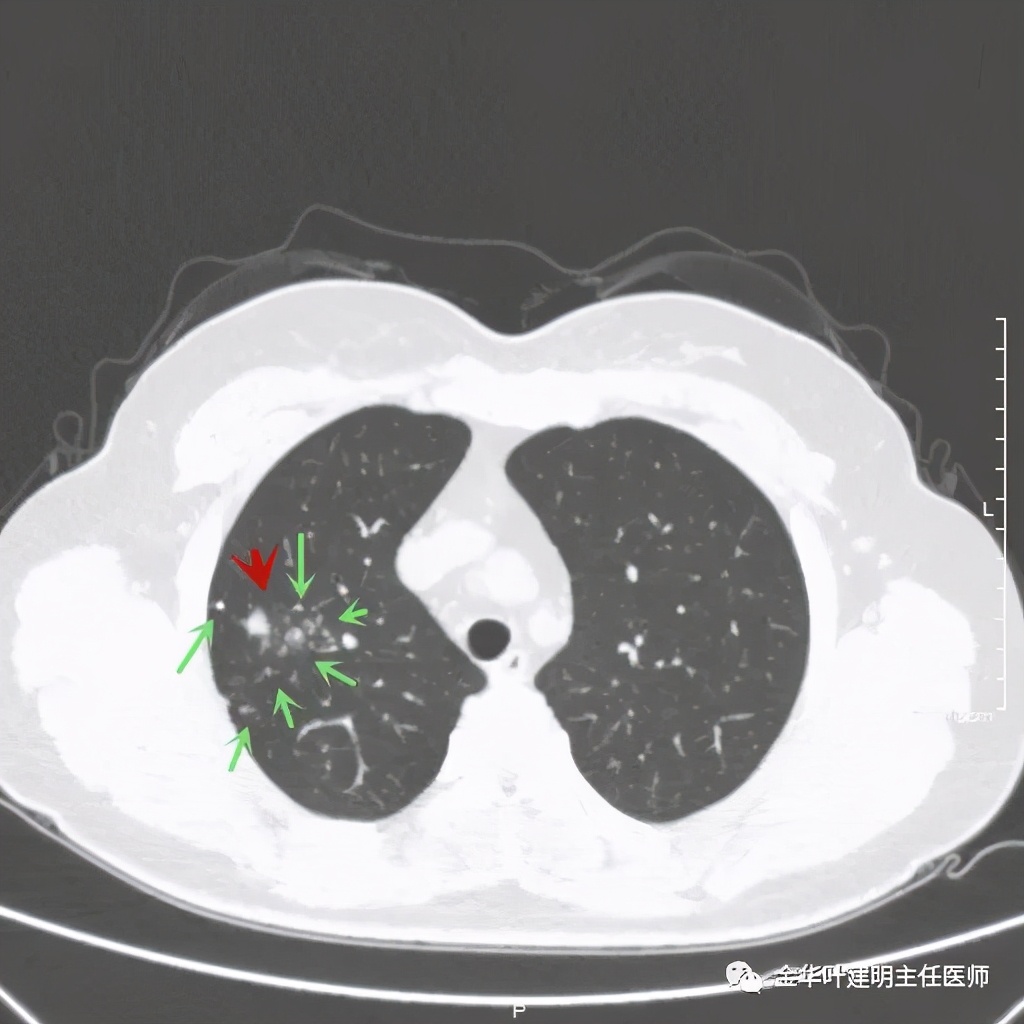

绿色箭头示主病灶边有小的实性微小结节,主病灶边缘非常光滑,没有毛刺、分叶等征

绿色箭头示病粉旁边有卫星灶,而且密度都高,主病灶也是实性

病灶边散在多发微小实性与似磨玻璃的微小结节

病灶附近不清爽